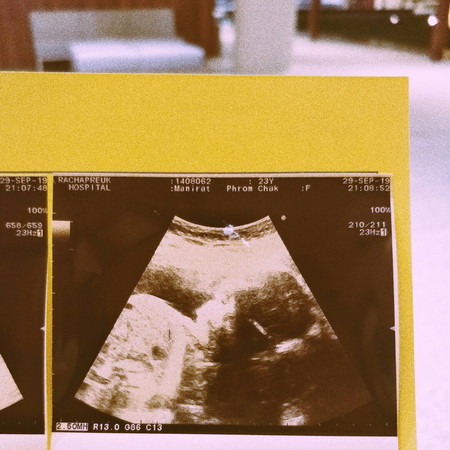

วันนี้ขอหมออัลตร้าซาวอีกรอบ เพื่อขอความชัดเจนเรื่องเพศของลูก สรุปได้ลูกสาวค่า ? ถ้าใครสังเกตดีดี นางหันมาเล่นกล้องด้วยนะ55555